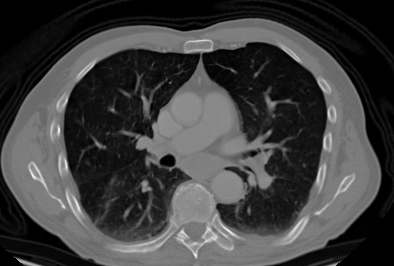

We propose a novel continual self-supervised learning (CSSL) framework for simultaneously learning diverse features from multi-window-obtained chest computed tomography (CT) images and ensuring data privacy. Achieving a robust and highly generalizable model in medical image diagnosis is challenging, mainly because of issues, such as the scarcity of large-scale, accurately annotated datasets and domain shifts inherent to dynamic healthcare environments. Specifically, in chest CT, these domain shifts often arise from differences in window settings, which are optimized for distinct clinical purposes. Previous CSSL frameworks often mitigated domain shift by reusing past data, a typically impractical approach owing to privacy constraints. Our approach addresses these challenges by effectively capturing the relationship between previously learned knowledge and new information across different training stages through continual pretraining on unlabeled images. Specifically, by incorporating a latent replay-based mechanism into CSSL, our method mitigates catastrophic forgetting due to domain shifts during continual pretraining while ensuring data privacy. Additionally, we introduce a feature distillation technique that integrates Wasserstein distance-based knowledge distillation (WKD) and batch-knowledge ensemble (BKE), enhancing the ability of the model to learn meaningful, domain-shift-robust representations. Finally, we validate our approach using chest CT images obtained across two different window settings, demonstrating superior performance compared with other approaches.